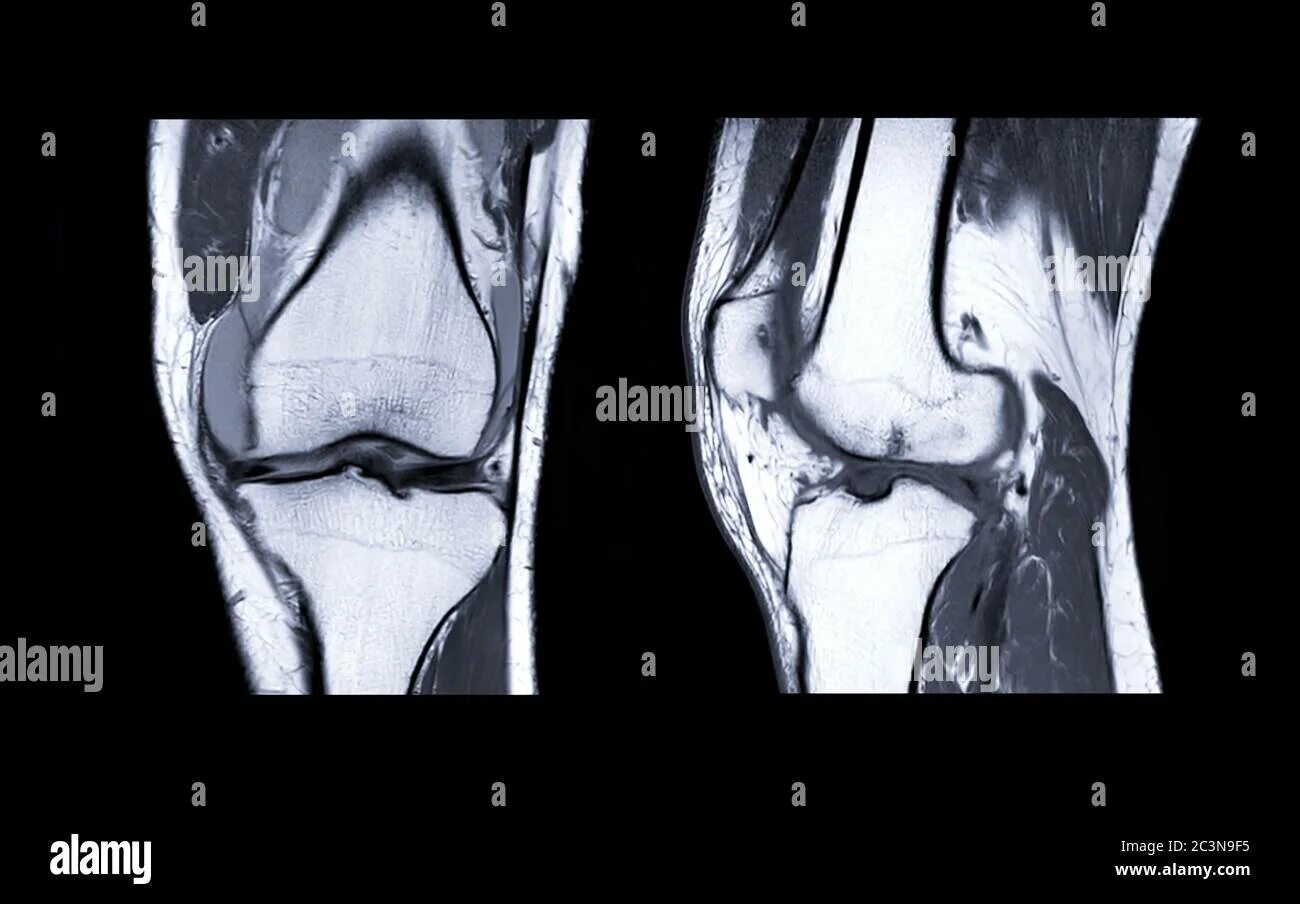

Мрт при боли в суставах